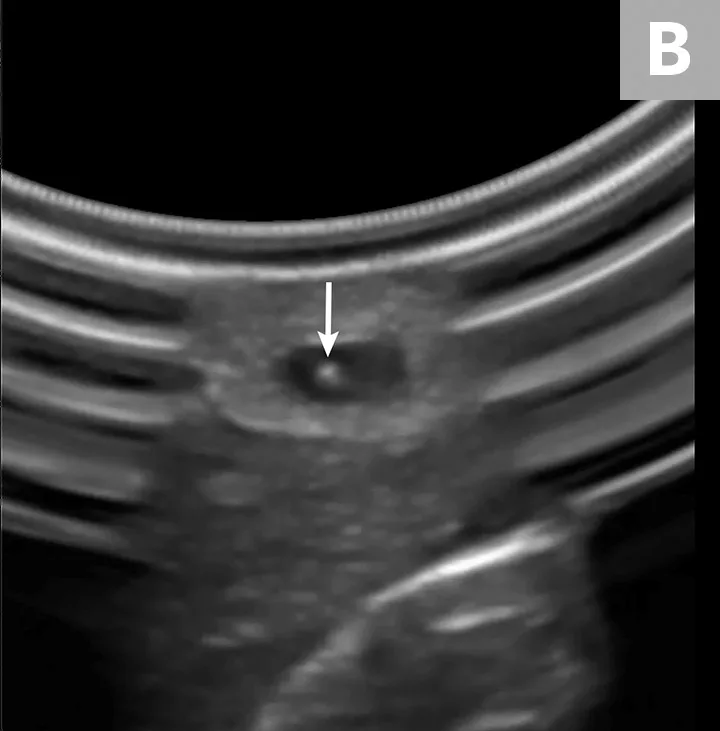

Full-body x-ray of neonate with intraosseous needle in place within femur.

The IO cavity is a noncollapsible space that allows direct IV access. Clinical indications for IO access include vascular collapse, severe vascular trauma, peripheral edema, thrombosis, and small patient or vessel size.2 Common locations for IO devices include the femoral intertrochanteric fossa in neonates (Figures 1 and 2) and the proximal humerus (Figure 3) and tibial tuberosity (Figure 4) in adult patients.2 Although research has not been conducted for all drugs and fluids, recommendations in human medicine support the same doses via IO and IV routes.4 Potential complications include fracture or bone infection at the access site, edema, fat embolism, nerve injury, or compartment syndrome.2 Contraindications include orthopedic surgery, skin infection, neoplasia, severe pre-existing bone disease, or prior IO access within 24 hours in the target extremity.

If desired, use radiography to confirm placement.